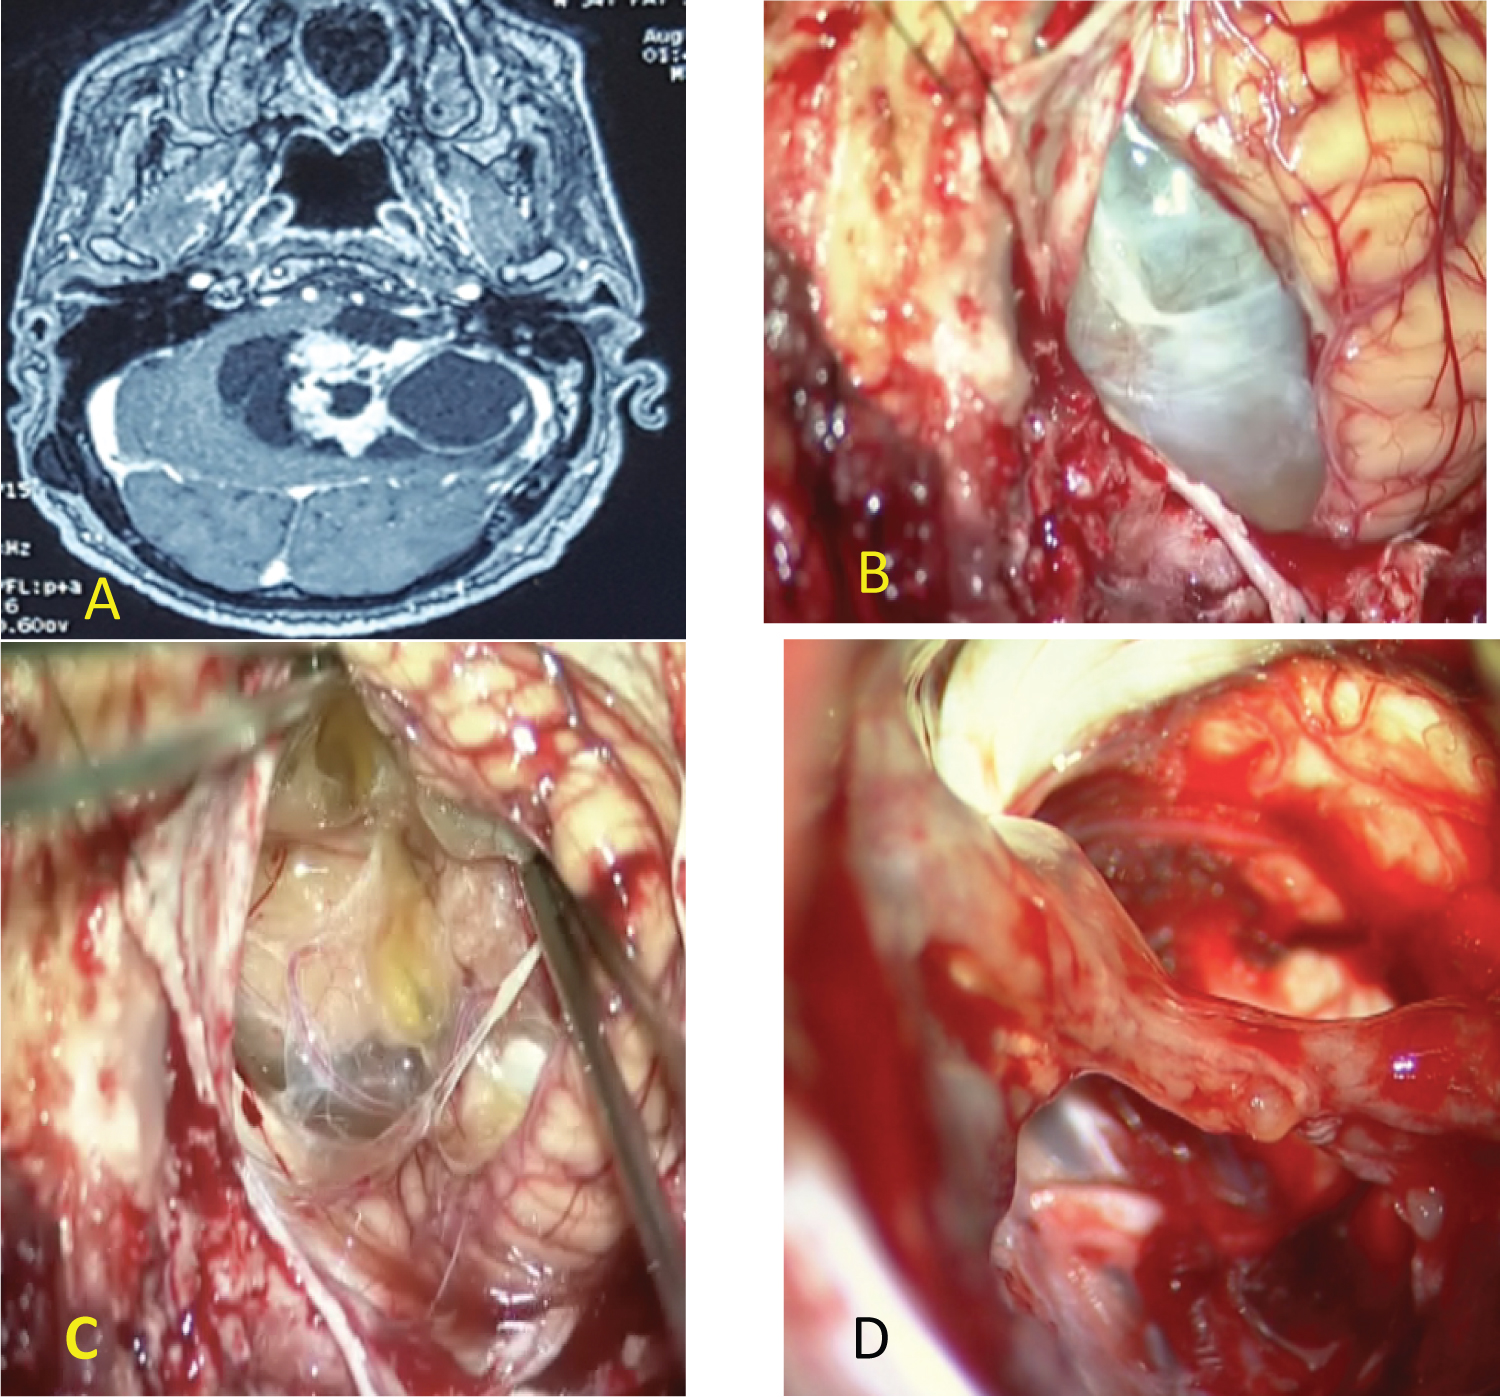

- In the second situation, to expose the tumor the cerebellum must be retracted with a narrow brain retractor and with a fine bayonet forceps the cerebellomedullary cistern was opened. The drainage of cerebro- spinal fluid (CSF) eased the cerebellum retraction: 11 cases (Figure 2).

Figure 2: (A) MRI of giant cystic VS type B (PC); (B) Evidence of the cyst wall after cerebellum retraction; (C) anatomic preservation of facial and cochlear nerve and a thin layer of tumor was left over the facial nerve; (D) postoperative MRI showing near total resection of cystic VS. View Figure 2

In cystic VS type A (PC) [3], identification and dissection of the facial nerve is less difficult in 03 cases (Figure 3). In type B (PC) the cyst is peripheral with a thin and fragile wall, making the establishment of a dissection plane more difficult (Figure 1 and Figure 2). When the facial nerve strongly adheres to the tumor, a thin layer of the tumor is left in place to preserve its integrity and especially its function 03 cases. In 2 cases the facial nerve was identified at the level of the brainstem but its identification on the wall of the cyst was impossible. For these 2 patients we proposed a facio-hypoglossal anastomosis.

Figure 3: (A) MRI of giant cyst VS; (B) CT scan: Postoperative hematoma; (C) Postoperative MRI with great total tumor resection. View Figure 3

The extent of tumor resection will be assessed, based on the postoperative MRI performed 1 month after surgery. Total resection was performed in 09 cases and in 03 cases total tumor resection was not possible and a thin layer of the tumor was left on the facial nerve (Figure 1 and Figure 2): Within the meatus in one case, and along the facial nerve in one case.